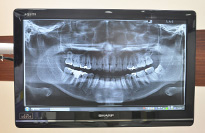

レントゲン写真

レントゲンや口腔内カメラで撮った写真は各診療台のモニターに映して丁寧に説明します。